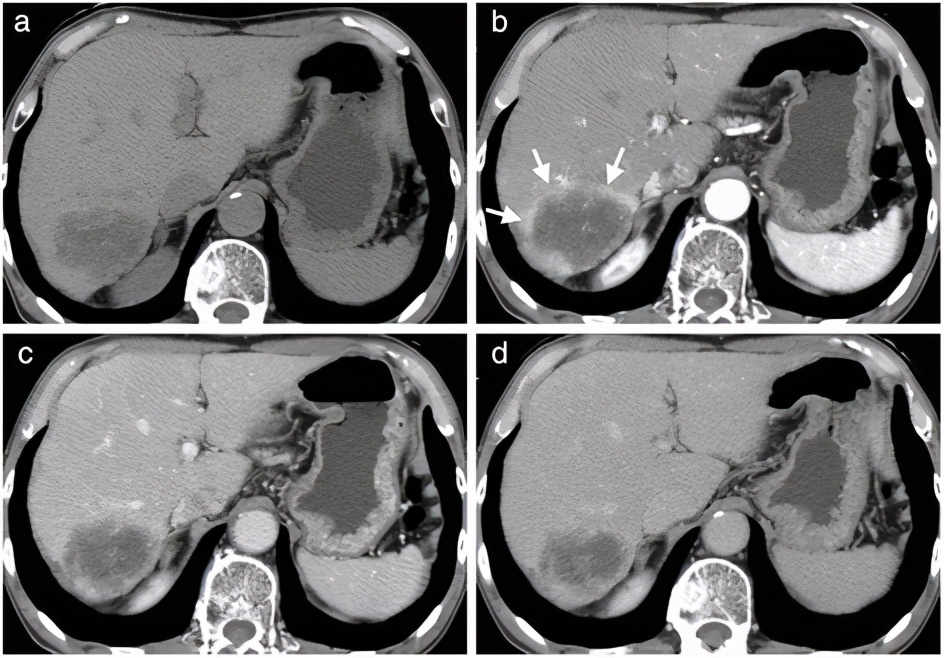

CT

要看清楚我们,CT检查是更清楚的。在CT下的我们,也是边界清楚的,呈低密度的肿块。大约10%的我们,可以同时发现里面有一些钙化灶。

磁共振

磁共振是更准确的无创性检查,检查的敏感性和特异性都是很高的,表现为呈边界清楚的、光滑的、均匀性质的肿块。但也有一些会跟血液供应丰富的癌症转移灶类似,要引起注意。

血管造影的检查,对于做增强CT和磁共振仍然不能确诊的,或者有恶性肿瘤病史和慢性肝病史者,怀疑不是血管瘤的,可能需要做血管造影。